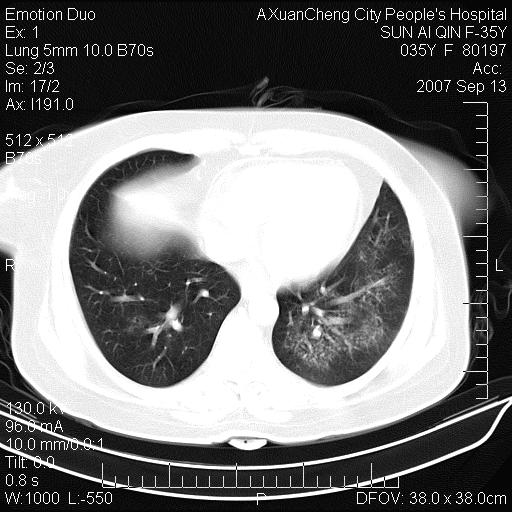

以下是引用天南地北在2007-9-13 13:43:00的发言:[br]考虑双肺、肺门侵润

以下是引用ydx_74在2007-9-13 15:42:00的发言:[br]仅看片,考虑右上肺癌并双肺转移,结合病史,考虑肺门、肺内淋巴侵润

以下是引用同在2007-9-13 15:08:00的发言:[br]支持肺门及双肺侵润.